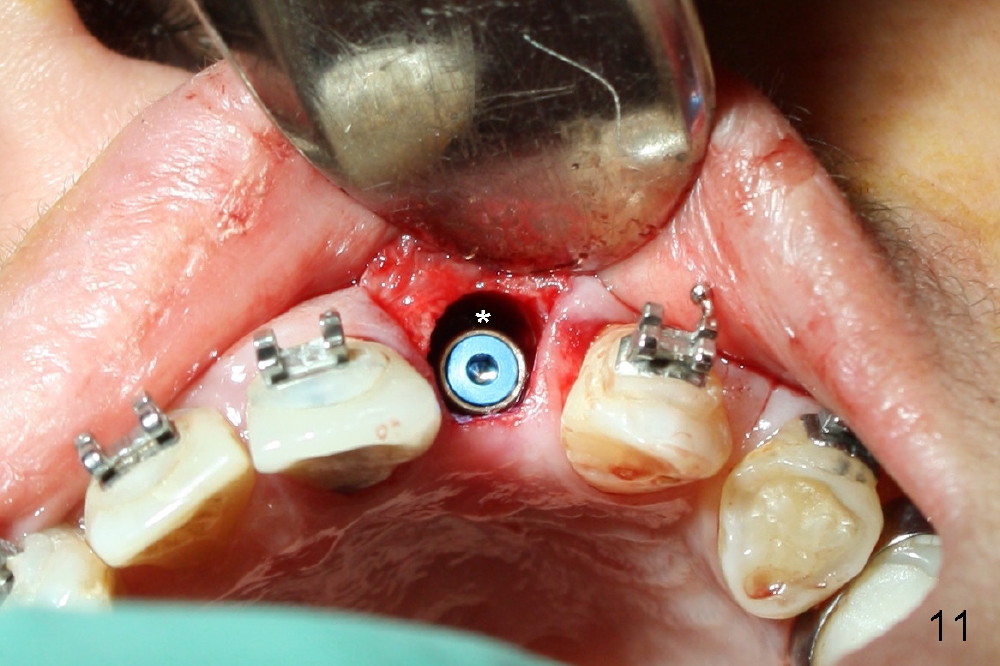

A 56-year-old Oriental lady is going to have immediate implant for the upper left lateral incisor after lengthened preparation (1 2 3 4). There is an indistinct fistula (Fig.1 <) and purulent discharge on anesthetic injection (Fig.2 <). The residual root is exposed (Fig.3 *) following a trapezoidal incision (arrowheads). After tooth extraction and socket debridement with a serrated curette (Fig.4), copious irrigation is conducted with a large monojet and normal saline (Fig.5). The socket will be soaked with non-woven gauze saturated with Clindamycin (Fig.6). The advantage of this antibiotic over Amoxicillin is that there is less mess with the former (completely dissolves). But Clindamycin is bitter. This amalgam well is saved to keep autogenous bone from the reamer and mix with allograft if needed.

The buccal gap (Fig.11 *) is to be filled by allograft before insertion of an angled abutment (3.9 mm 25 º 3 mm cuff, Torx A type, Fig.12). The shoulder of the abutment is at the crest level (*). A longer cuff (4 or 5 mm) would be more appropriate. The gap buccal to the shoulder of the abutment is closed by further bone graft. An immediate provisional is fabricated (Fig.12 P), followed by suturing the buccal flap (*), which should give bulk of the gingival tissue.